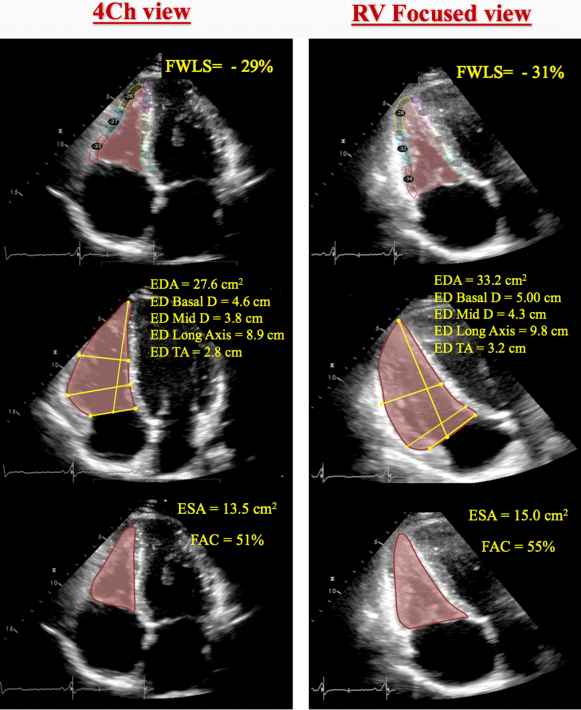

The conventional apical four-chamber view (i.e., focused on the left ventricle) results in considerable variability in how the right heart is sectioned, and consequently, RV linear dimensions and areas may vary widely in the same patient with relatively minor rotations in transducer position (Figure 7B). RV dimensions are best estimated from a RV-focused apical four-chamber view obtained with either lateral or medial transducer orientation (Figure 7A and Table 7). Care should be taken to obtain the image with the LV apex at the center of the scanning sector, while displaying the largest basal RV diameter and thus avoiding foreshortening. Of note, the accuracy of RV measurements may be limited when the RV free wall is not well defined because of the dimension of the ventricle itself or its position behind the sternum. Recent data have suggested that indexing RV “size” to BSA may be relevant in some circumstances, but the measurements used in those studies lacked the reference points of the RV-focused view and frequently used RV areas, rather than linear dimensions. 1

In general, a diameter >41 mm at the base (widest part of the basal 1/3rd of the RV; do NOT measure at the annulus) and >35 mm at the midlevel in the RV-focused view indicates RV dilatation. 1

- 🌟RV focused A4C View: LV apex is at the top of the view, but angulated transducer to tip the RV into better view. This view allows you to measure the maximal RV diameter.

- This is the view that you will want to use to take measurements for RV size

See the following image from 2 that helps illustrate the importance of getting the optimal view for RV size assessment:

- Obtain in RV focused A4C view

- Values < 35% are consistent with RV dysfunction

Longitudinal strain is calculated as the percentage of systolic shortening of the RV free wall from base to apex, while longitudinal strain rate is the rate of this shortening. 1

- Abnormal if values are less negative than -25% (or lower than 25% in absolute value)

- Should be measured in the RV-focused A4C view